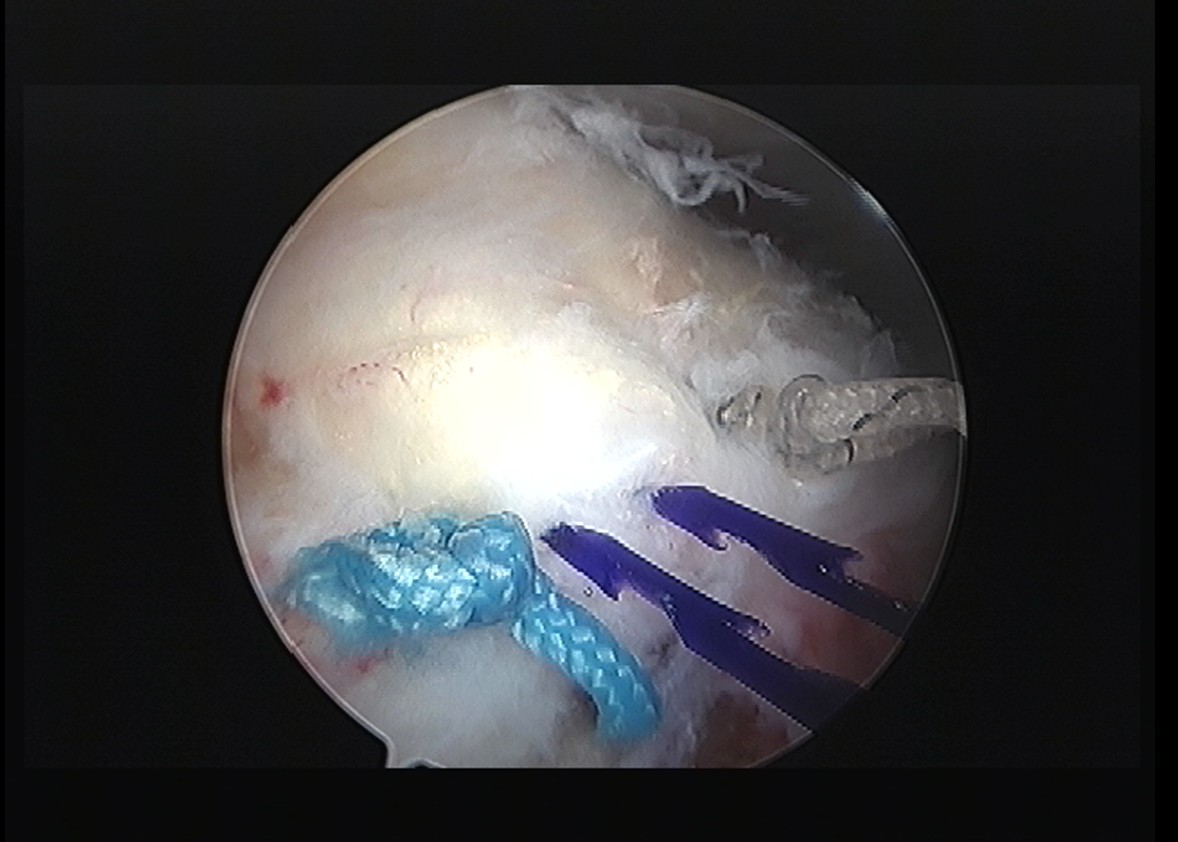

시술 과정

시술 시간: 약 50분 (석회 제거 30분 + 봉합술 20분)

시술 시간: 약 40분

시술 시간: 약 35분